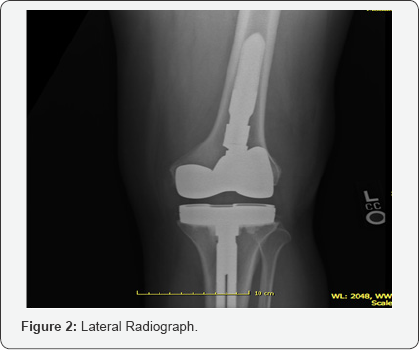

Upon physical examination, it was noted that the patient had a large joint effusion on the left knee and was slightly warm to touch when compared to contralateral knee. The incision site had healed with a supple scar and good cosmesis. Focal tenderness to palpation was noted over medial and lateral femoral condyle. Range of motion was 0-105 degrees measured with a goniometer. The patient had well balanced ligaments throughout arc of motion with appropriate patella tracking and no subsequent subluxation or dislocation. Longstanding lower extremity radiographic evaluation showed 1.3 degree valgus mechanical axis with 91.5 degree medial femoral articular angle and a 90 degree medial tibial articular angle. Radiographs including AP/ Lateral/merchant views showed overhang of lateral aspect of femoral component. Tibial component was well sized. The joint line and patella height appeared within normal limits.

The initial plan was to perform a basic infectious workup with erythrocyte sedimentation rate (ESR) and C-reactive protein (CRP). Knee arthrocentesis was performed and sent for synovial fluid cell count with differential, gram stain, culture and sensitivities, crystal analysis, alpha defensin, synovial CRP and human neutrophil elastase testing. Results revealed an ESR of 60 (normal range 0-22), and a CRP of 1.03 (<.8 normal). Cell count with differential was 606 white blood cell counts with 15% segmented neutrophils which decreased the likelihood of prosthetic joint infection. Crystal analysis was negative and final cultures showed no growth. Synovial CRP, alpha defensin and human neutrophil elastase testing were negative or within normal limits. The patient returned three weeks later with knee pain out of proportion to what would be expected for oversized or malpositioned components. ESR and CRP were again repeated with similar results. A metal allergy serum assay was ordered to rule out metal hypersensitivity. One month later, the results of the metal allergy testing did show reactivity to nickel. The patient elected to proceed with TKA revision with oxidized zirconium (Oxinium, Smith & Nephew) hypoallergenic components. (Figures 1-4) Postoperative lower extremity radiographs.

On subsequent postoperative visits, patient progressed well and was ambulating with a cane by 8 weeks. His pain was overall improved and he had an arc of motion of had 0-110 degrees of flexion. The knee was stable to varus and valgus stress. At 20 weeks postoperative, the patient continued to progress well. Passive range of motion was 0-110 degrees and full strength in quadriceps and hamstring was noted. Radiographs showed overall well sized and well positioned components.